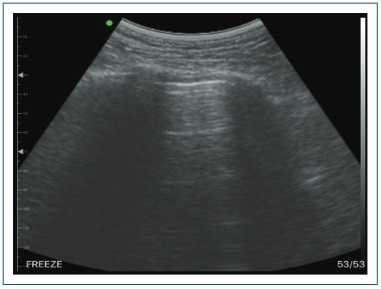

Son las principales líneas o artefactos horizontales, de características hiperecogénicas y repetición de la línea pleural. Mantienen la misma distancia a la línea pleural y entre cada línea A. Las líneas A representan aire en la pleura. Puede ser aire alveolar, que corresponde al funcionamiento normal pulmonar (Fig. 2).36,37

Líneas A.